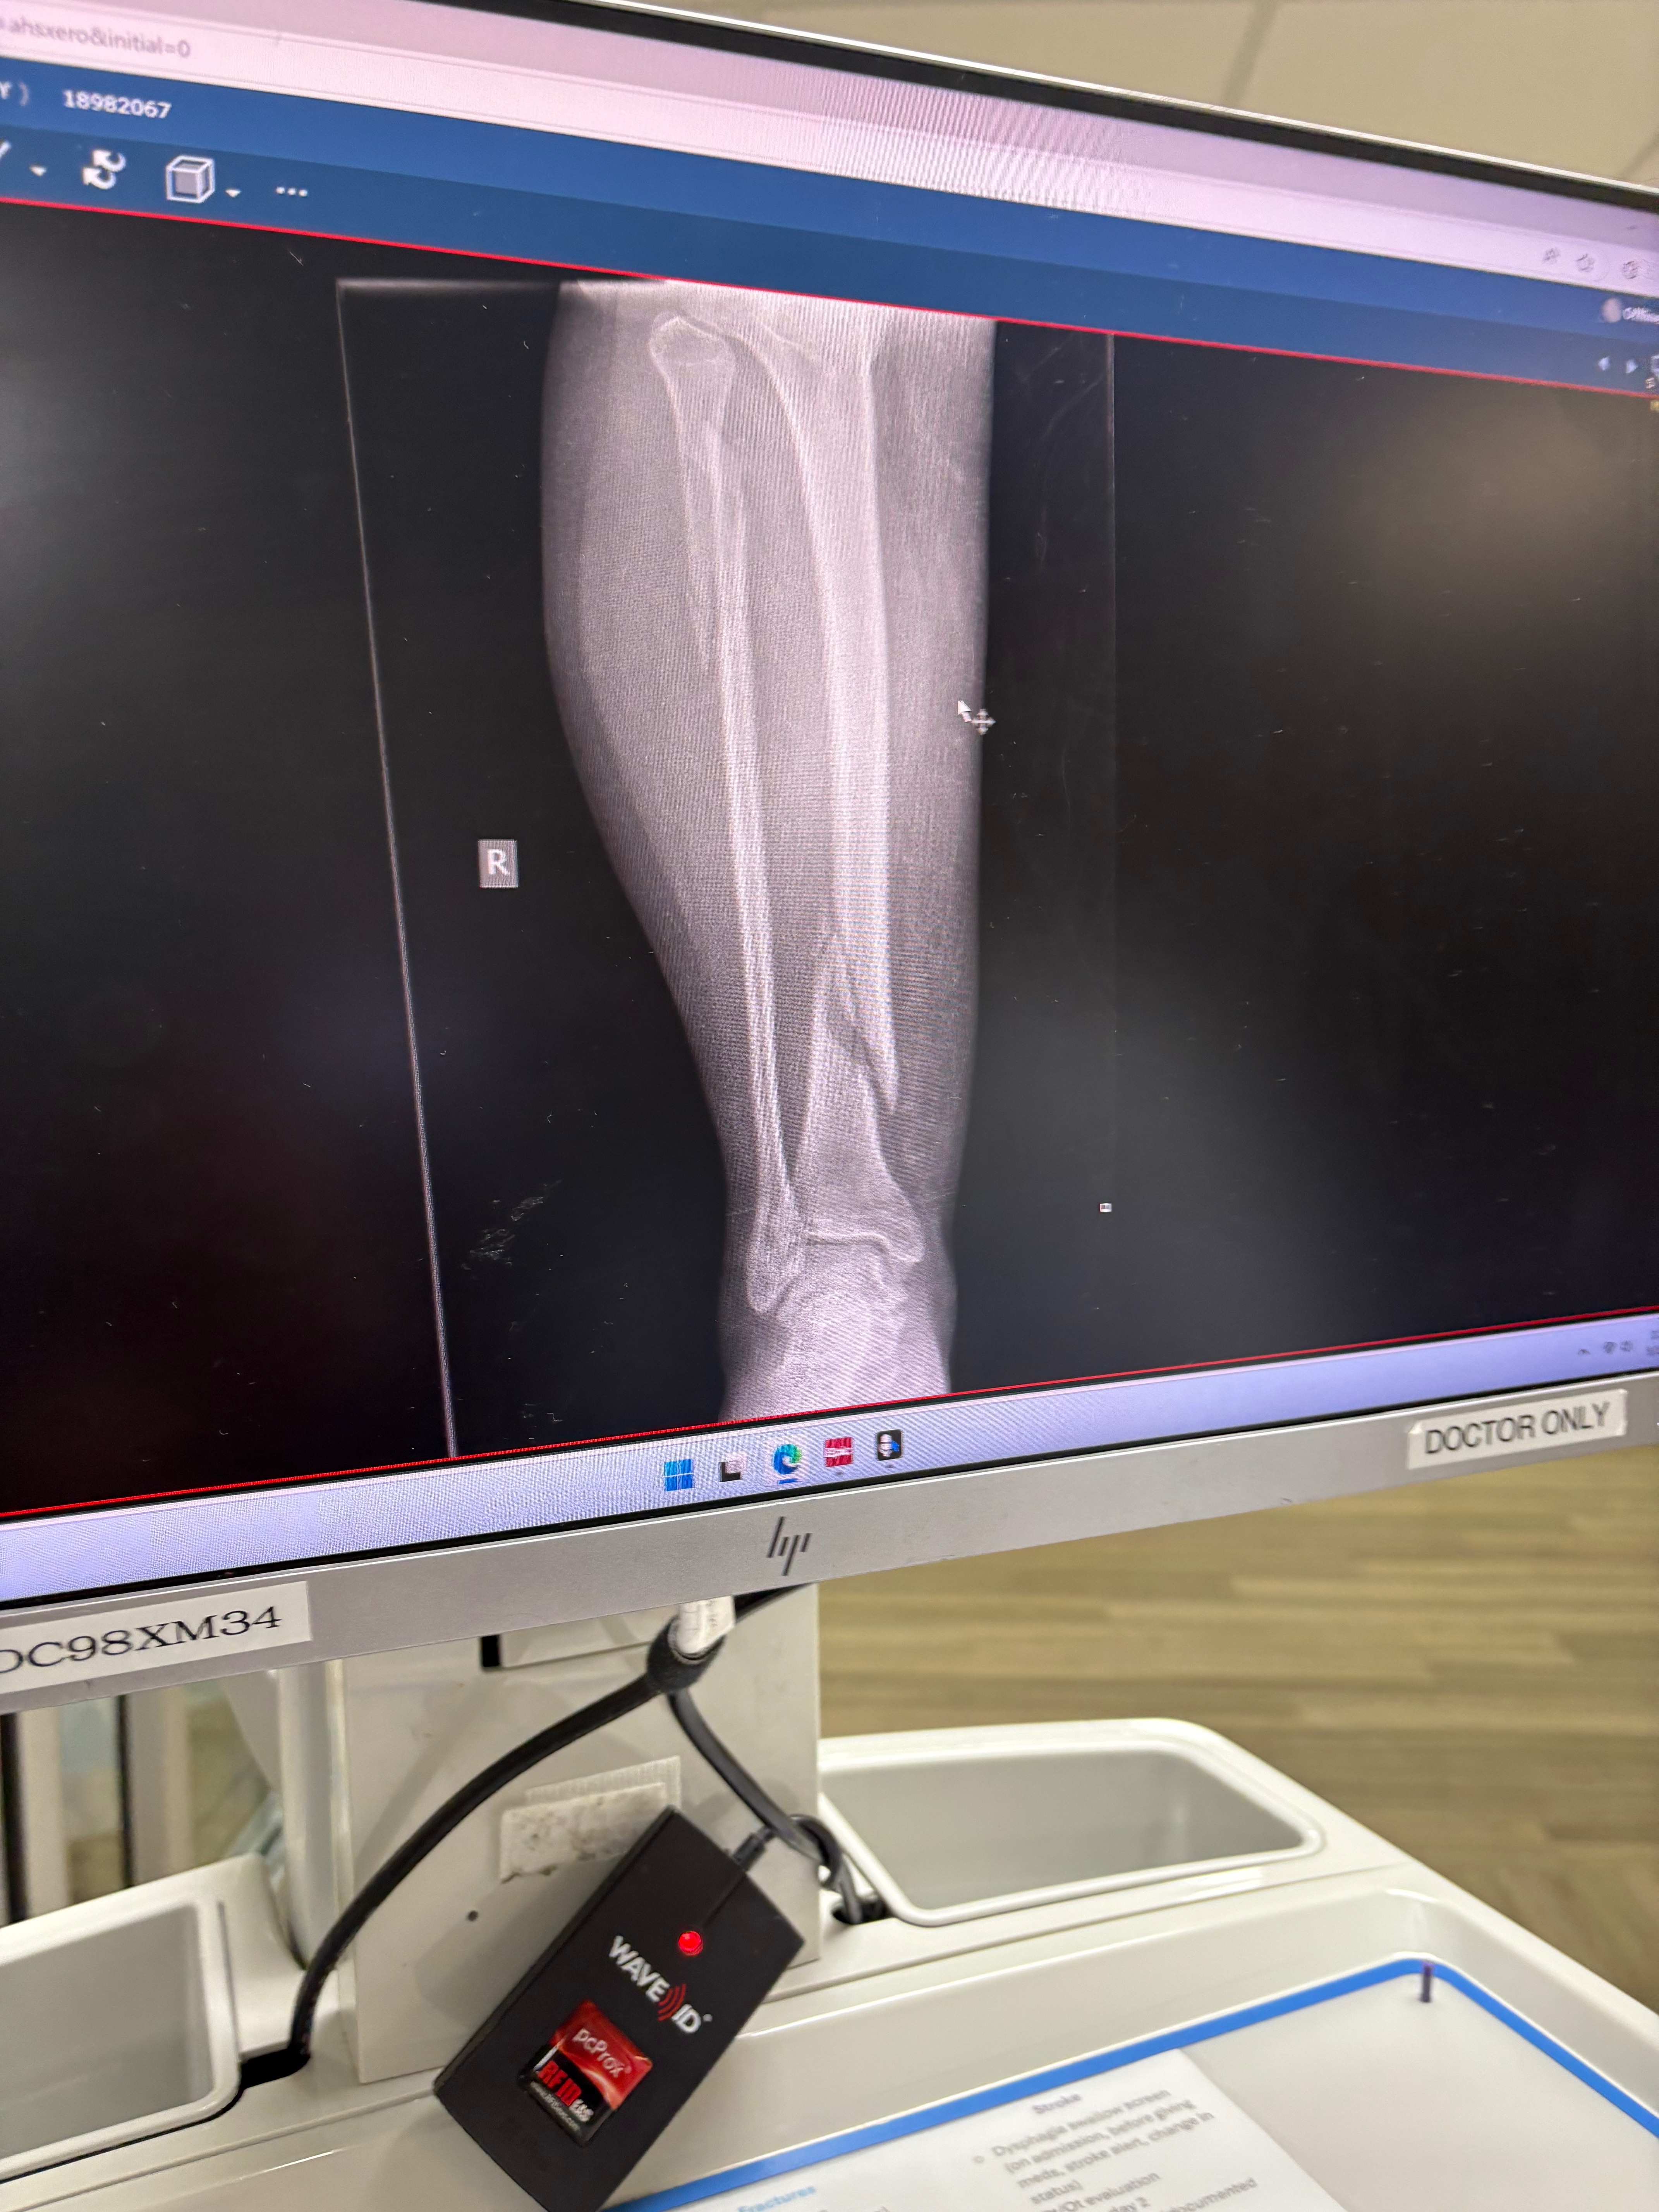

Hi, my name is Denny. On Friday, 5/2, my husband fell, resulting in him having to be rushed into surgery. He broke his ankle in two different spots and has a fracture on another part. He spent 6 hours in surgery and he needs to spend 3 weeks in rehab. We have two beautiful kids at home that we need to support. This emergency has put a strain on us as a family, but we are doing our best to get through it. I currently have two jobs, but now with my husband being injured, I may have to take up a third. He will be out of work for 3 months and my income alone is not enough to support my family through this. I’m putting my pride aside for the sake of my husband and kids to ask for help. Any little amount helps. It will be going to 3 months' worth of bills, food, medical expenses, and anything my kids may need during those months.